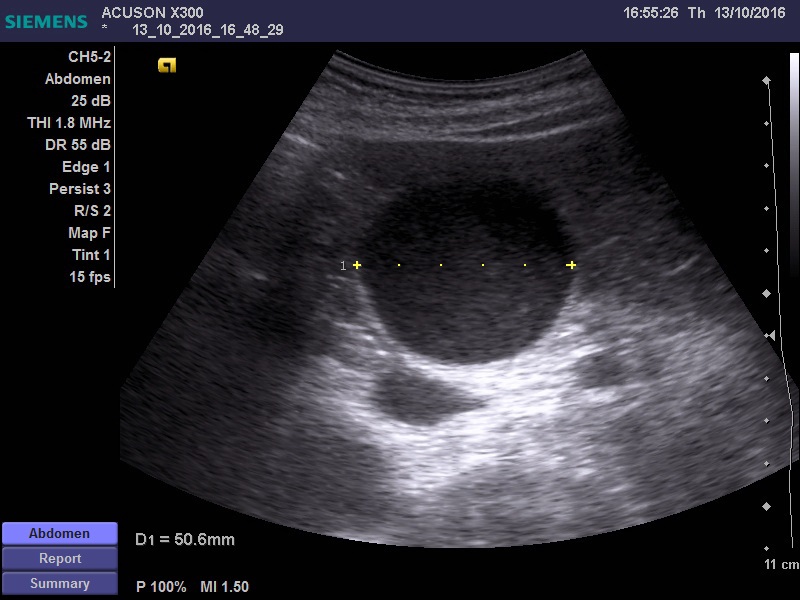

Дедушка лет 80, поступил по скорой с жалобами на боли в животе, провели узи, увидели выраженный асцит. Затем кто то видимо подсобрал анамнез, поставил катетер в мочевой и вывел 4 литра мочи. Для того что бы исключить хир. патологию и отправить дедушку на излечение в урологию повторно проведено уз исследование.

желчный пузырь увеличен 11*5 см, заполнен крупнодисперсной взвесью, в области шейки свободная жидкость. Дискинезия ЖВП?

Не видно причины гипертензии за уровне шейки ЖП -- холедоха, но признаки гипертензии есть.

есть признаки да. учитывая гемодинамически значимый стеноз ВБА, я бы склонился к эмпиеме пузыря, на фоне атеросклеротических изменений пузырной артерии. Учитывая возраст, клиника может быть стёрта, а учитывая наличие свободной жидкости, можно подумать о вялотекущей ишемии стенки и нарастающей деструкции. Я так бы рассудил.

Ишемический некроз стенки желчного пузыря теоретически может быть и он очень плохо диагностируется при УЗИ.

Но должны быть другие признаки воспаления, например, околопузырный инфильтрат и хоть какое-нибудь изменение стенок.